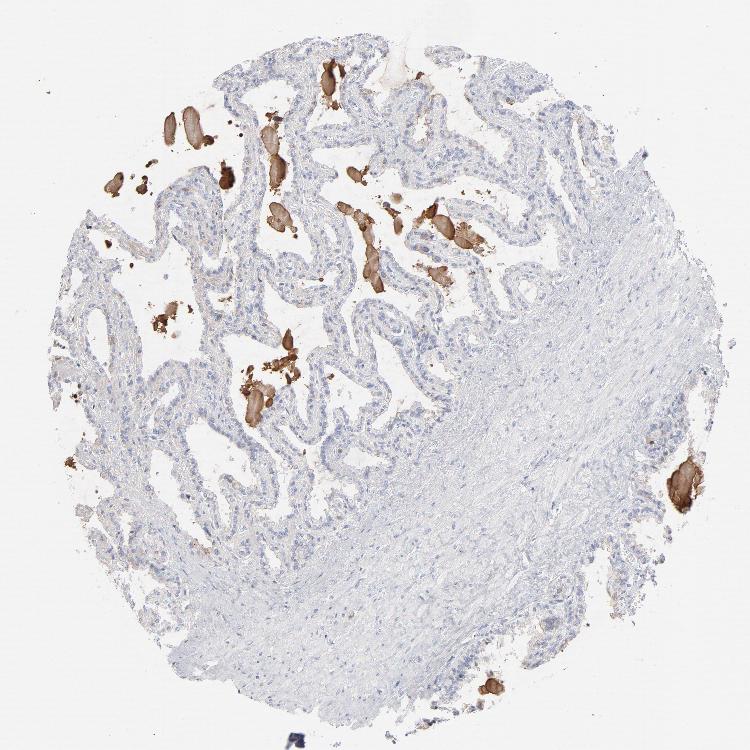

SEMINAL VESICLE - Antibody stainingi

Antibody staining in the annotated cell types in the current human tissue is reported as not detected, low, medium, or high, based on conventional immunohistochemistry profiling in selected tissues. This score is based on the combination of the staining intensity and fraction of stained cells.

Each image is clickable and will lead to virtual microscopy that enables deeper exploration of all samples and also displays staining intensity scores, fraction scores and subcellular localization as well as patient and tissue information for each sample.

Antibody HPA003898Antibody CAB002163Antibody CAB016312

Glandular cells Not detectedLowNot detected